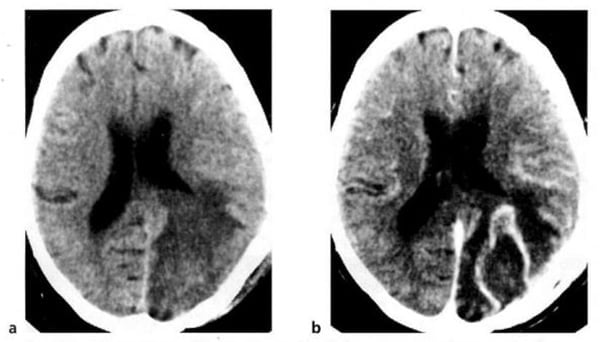

Hình 1.32. U nguyên bào đệm đa dạng. Hình ảnh trước tiêm (a) là tổn thương mật độ thấp ở hai bên đường giữa. Ở thùy trán bên trái còn có một tổn thương mật độ cao (xuất huyết). Sau tiêm (b), bắt chất cản quang mạnh, dạng viền.